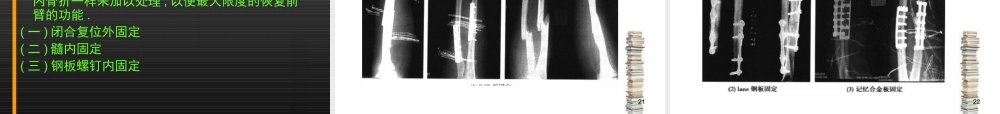

1前臂骨折前臂骨折2目录前臂的功能解剖和生物力学Monteggia骨折Galeazzi骨折桡骨干骨折尺骨干骨折前臂双骨折3前臂的功能解剖和生物力学1桡骨2尺骨3桡尺骨的连接4前臂的旋转肌4一:前臂的功能解剖和生物力学前臂由尺桡骨组成,两骨借骨间膜相连.近侧,尺桡骨形成上尺桡关节;远侧,形成下尺桡关节,是前臂旋转功能的重要解剖基础.(一)桡骨1桡骨的解剖2旋转弓5一:前臂的功能解剖和生物力学桡骨本身具有两个弯曲,称为旋转弓.桡骨颈向远侧及尺侧斜行,桡骨干的近侧则向远侧及桡侧斜行,两者之间形成了一个夹角,称旋后弓,恰处于桡骨粗隆的水平.桡骨干的远侧斜行向远侧及尺侧,因之与近侧段之间又形成了一个夹角,称旋前弓,此角恰处于旋前圆肌粗隆处.6一:前臂的功能解剖和生物力学(二)尺骨1:尺骨的解剖2:尺骨截面呈三角形,全长均处于皮下,因而易造成开放骨折.(三)桡尺骨的连接1:前臂骨间膜---致密的纤维结缔组织,膜状,远近侧均较薄弱,中部厚韧.7一:前臂的功能解剖和生物力学8一:前臂的功能解剖和生物力学2:上尺桡关节连同肱尺关节,肱桡关节一同构成肘关节.三组关节包于一个关节囊内构成,关节囊附着于各关节面附近的骨面上,肱骨内、外上髁均位于囊外。关节囊前后松弛薄弱,两侧紧张增厚形成侧副韧带。尺侧副韧带呈三角形,起自肱骨内上髁,呈放射状止于尺骨滑车切迹内侧缘,有防止肘关节侧屈的作用。桡侧副韧带也呈三角形,附于肱骨外上髁与桡骨环状韧带之间。此外,在桡骨头周围有桡骨环状韧带,附着于尺骨的桡骨切迹的前后缘,此韧带同切迹一起形成一个漏斗形的骨纤维环,包绕桡骨头。4岁以下的幼儿,桡骨头发育不全,且环状韧带较松弛,故当肘关节伸直位牵拉前臂时,易发生桡骨头半脱位。由于关节囊后壁最薄弱,故临床常见桡尺骨向后脱位.当肘关节伸直时,肱骨内、外上髁与尺骨鹰咀尖恰位于一条直线上,屈肘时则形成以鹰咀尖为顶角的等腰三角形,临床上常以此鉴别肘关节脱位.9一:前臂的功能解剖和生物力学103一:前臂的功能解剖和生物力学11一:前臂的功能解剖和生物力学3:下尺桡关节由桡骨的尺骨切迹与尺骨头的环状关节面,以及尺骨头下方的三角形关节盘共同构成.关节囊较松弛,附着于尺骨切迹和尺骨头的边缘,其掌侧和背侧有下尺桡前后韧带加强。12一:前臂的功能解剖和生物力学(四)前臂的旋转肌前臂的旋转肌按其功能分组前臂的旋转肌旋前肌组1:旋前方肌2:旋前圆肌旋后肌组1:旋后肌2:肱二头肌单击添加13一:前臂的功能解剖和生物力学(四)前臂的旋转肌单...